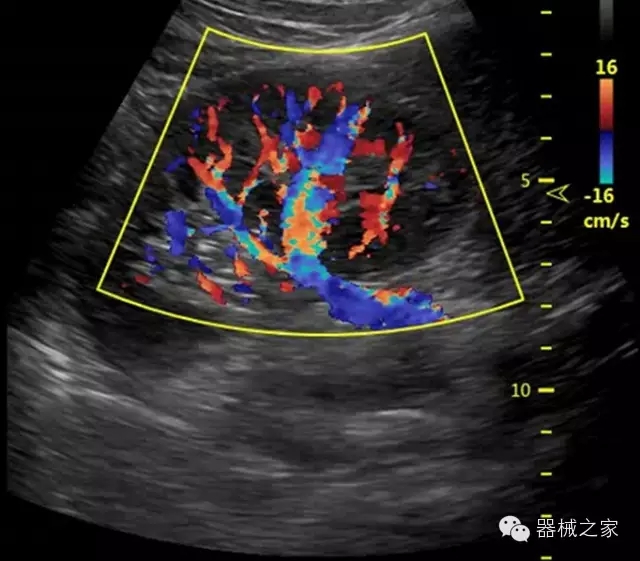

臨床圖片賞析

·獨(dú)有RF敏感血流使得心臟血流完美呈現(xiàn);